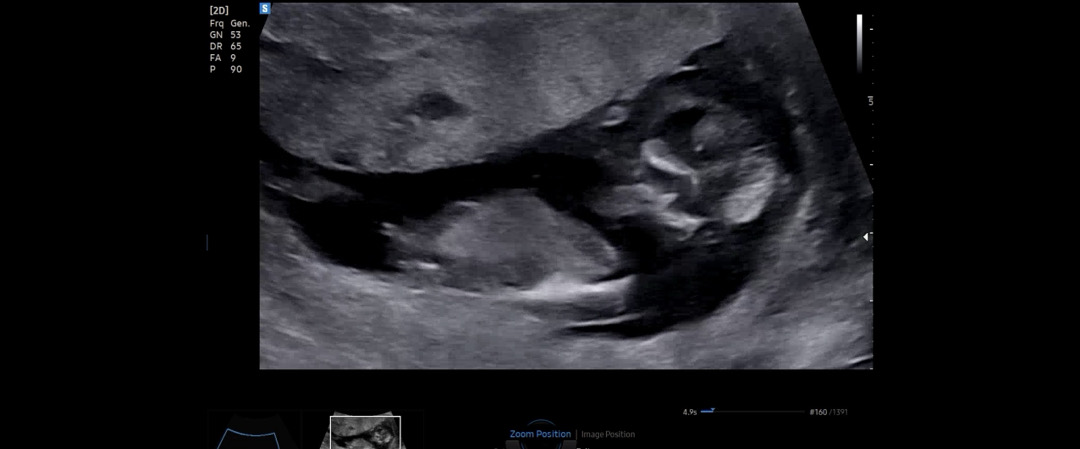

12주 1일 각도법 봐주세요🥹🙏🏻💕

딸일까요 아들일까요?? 둘째라 너무 궁금해요ㅠㅠ